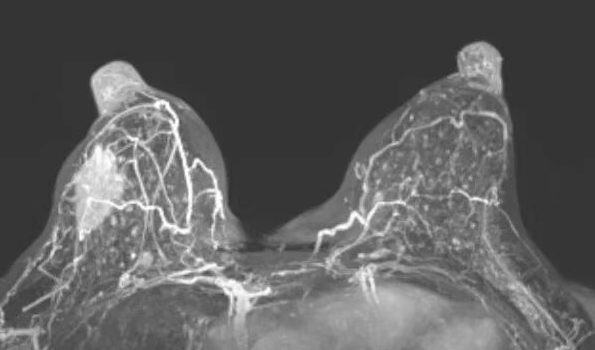

在靶区固定环节,中心采用自主研发的乳腺固定器(实用新型专利号:ZL202221125437.4)联合负压垫、热塑体膜的三重固定技术,从源头上解决靶区移位难题,为精准放疗筑牢基础。剂量方案上,摒弃日本单一剂量模式,根据肿瘤大小、距皮肤距离、病理类型等个体差异精准制定:肿瘤靶区给予72-80Gy(RBE)根治剂量,全乳及淋巴引流区给予40Gy(RBE)预防剂量,阳性淋巴结按大小调整为48-60Gy(RBE)。同时,通过多野照射技术优化剂量分布,最大限度降低皮肤受照剂量,显著减少放射性皮炎等并发症风险,真正实现“精准杀伤肿瘤、严格保护正常组织”的双重目标。